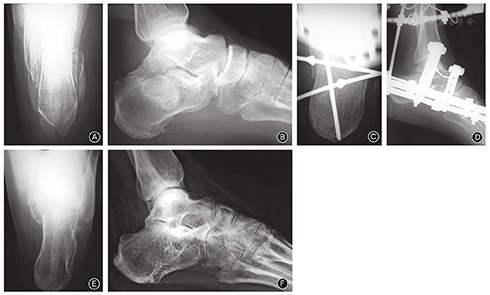

跟骨长度支架组(63.23±5.67)mm小于钢板组(63.59 ± 4.58)mm,但两组比较差异无统计学意义(P >0.05, 表5)。这说明在恢复跟骨长度方面,支架组疗效基本与钢板组相当(图1)。

Böhler角支架组(27.77°± 2.86°)小于钢板组(30.45°± 3.45° ),相差约3° ;Gissane角支架组(131.23°±3.92°)大于钢板组(127.82°±4.65°),相差约4°,两组Böhler角、Gissane角比较差异均有统计学意义(均P< 0.05,表5)。这说明在恢复跟骨高度及关节面对位方面,钢板组优于支架组。

轴位角支架组(19.23°± 2.20°)小于钢板组(22.64°±5.14°),相差约3°;足跟宽度支架组(33.61± 3.43)mm小于钢板组(36.05 ± 3.26)mm,相差约3 mm;两组轴位角、足跟宽度比较差异有统计学意义(均P< 0.05,表5)。这说明在恢复跟骨宽度及纠正内翻角度方面,支架组优于钢板组。